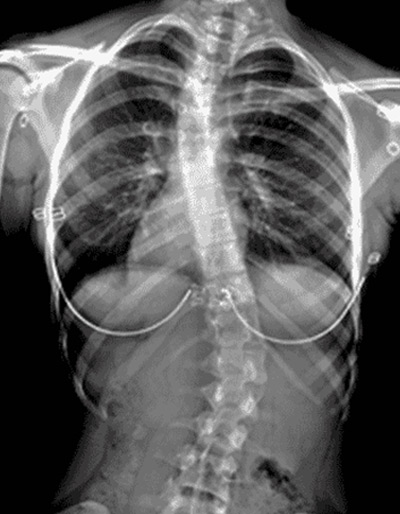

Espinografía

digital directa

Estudio de la columna vertebral completa para la evaluación de la morfología y curvaturas del raquis para su adecuada planificación terapéutica.